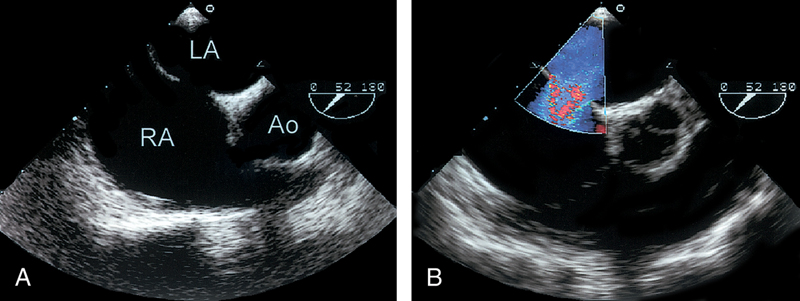

فحوصات تشخيصية لبعض امراض القلب والشرايين التاجية